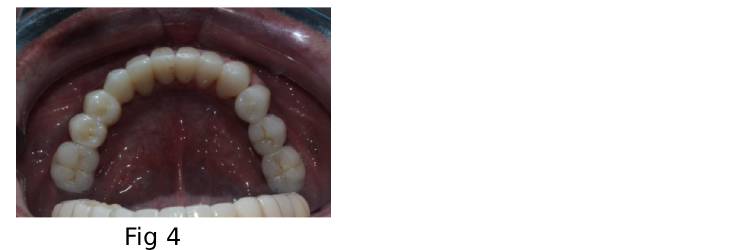

• The lower arch received a tooth supported Illusion Zirconia Dental Bridge for a more natural result. (Fig 4)

Occlusal view of the mandibular Illusion Zirconia Dental Bridge, demonstrating full-arch coverage and tissue adaptation.